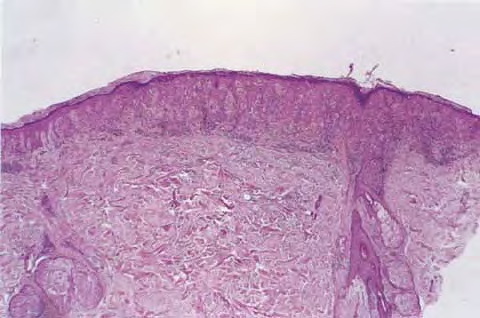

Architectural pattern features of importance in the diagnosis include the large diameter of the lesions, poor circumscription (the last cells at the edge of the lesion tending to be small, single, and scattered), and asymmetry (one half of the lesion does not mirror the other half) . The epidermis is irregularly thickened and thinned, in contrast to the uniformly elongated rete ridge pattern of a dysplastic nevus . Rather uniformly rounded, large melanocytes are scattered in a pagetoid pattern throughout the epidermis. The large cells lie predominantly in nests in the lower epidermis and singly in the upper epidermis. The nests tend to vary a good deal in size and shape and to become confluent. Dermal melanophages and a dermal infiltrate are regularly present. The lymphocytic infiltrate may be patchy and perivascular as in a dysplastic nevus but is typically dense and bandlike, especially in invasive lesions.

When the lesion is in situ, the basement membrane is intact  and there are no lesional cells in the dermis. In an invasive but nontumorigenic lesion (invasive radial growth phase or microinvasive melanoma), cells similar to those in the epidermis are present in the dermis in the form of small nests, with no nests larger than those in the epidermis, and with no dermal mitoses . When tumorigenic vertical growth phase is present, there is at least one, or often more than one, cluster of cells in the dermis that is larger than the largest intraepidermal nest, and/or there may be lesional cell mitoses in the dermis .